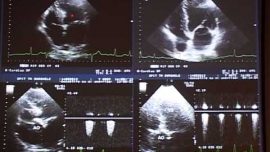

Este o investigaţie noninvazivă ce analizează structura şi funcţia cordului cu ajutorul ultrasunetelor.

Ce reprezinta o ecocardiografie?

Este principala metodă imagistică în cardiologie şi cea mai solicitată, permitand studierea şi vizualizarea amănunţită a tuturor structurilor cordului (cavităţile, valvele,septurile, muşchii). Datorită acesteia se pot cunoaşte cu precizie parametrii care definesc atât funcţia de contracţie, cât şi funcţia de relaxare a inimii. Cu ajutorul ei, poate fi măsurată grosimea pereţilor inimii, pot fi vizualizate şi diagnosticate corect leziunile valvulare, congenitale, miocardice. Nu în ultimul rând, ecografia permite şi analizarea pericardului (a învelişului în care se găseşte inima), iar o inflamaţie la nivelul acestuia poate fi usor depistata in unele cazuri.

Ca investigaţie, este valoroasă atât pentru stabilirea unui diagnostic iniţial, cat si urmarirea, aprecierea severităţii şi ghidarea tratamentului pentru majoritatea afecţiunilor cardiovasculare.

Întrucât utilizează ultrasunetele, ecocardiografia nu prezintă nici un risc pentru pacient, este nedureroasă, neinvazivă şi poate fi efectuată de câte ori aveţi nevoie (lucru pe care nu-l puteţi efectua la o tomografie computerizată, de exemplu). În plus, este recomandată oricărei persoane care are hipertensiune arterială, pentru a cunoaşte în ce măsură îi este afectată inima.Este folosită atât în urgenţele cardiovasculare, cât şi în bolile cronice.

Există mai multe moduri de examinare ecografică: ecografia în mod M, ecografia bidimensională, ecografia Doppler (pulsat, spectral şi color) şi ecografia tridimensională (3D). Toate aceste moduri dau informaţii complementare şi sunt folosite pentru o evaluare cardiacă completă, succesiv sau simultan.